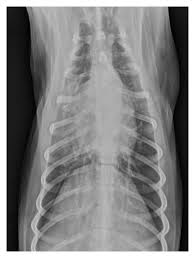

X rays are very helpful in the diagnosis of lung cancer in dogs. If you have lung cancer, it may be more difficult for your doctor to diagnose pneumonia. A white spot amidst the normal black lungs can therefore be a cancer, infection. Dog pneumonia or lung cancer. Pneumonia is a lung infection that leads to breathing difficulties and fluid in the lungs.

A definitive diagnosis of lung cancer requires a sample of tissue (biopsy). X rays are very helpful in the diagnosis of lung cancer in dogs. Primary lung cancer are frequently located in the caudal (towards the hind end of the pet) lung lobes, however can be located in any lung lobe and are usually a single mass in the lungs, unless the tumor has spread. If your dog has a chronic cough, you'll need to rule these out. The first of these possibilities could be investigated by bronchoscopy. A definitive diagnosis of lung cancer requires a sample of tissue (biopsy). The second kind of lung cancer in dogs is called metastatic lung cancer, which means the cancer originated somewhere else in the body, but has spread to the lung. Bacterial pneumonia is an inflammation of the lung usually caused by bacterial or viral infection but can be caused by inhalation of an irritant. The respiratory system consists of the large and small airways and the lungs. Lung cancer is actually the number one killer when it comes to cancers. But in some rare cases, it may be a lung cancer (primary or secondary). In both cases, you may have. Typical signs of bacterial pneumonia include fever, difficulty breathing, lethargy and coughing.

Primary lung cancer are frequently located in the caudal (towards the hind end of the pet) lung lobes, however can be located in any lung lobe and are usually a single mass in the lungs, unless the tumor has spread. My dog had pneumonia come on quickly this last august, we took her to the local er at 3am when we noticed her breathing labored and strange behavior. A white spot amidst the normal black lungs can therefore be a cancer, infection. Signs of the primary tumors in dogs. I haven't touched cigarettes a day in my life. Lung cancer often misdiagnosed as pneumonia urges requests for second medical opinions. Lung cancer is actually the number one killer when it comes to cancers. A definitive diagnosis of lung cancer requires a sample of tissue (biopsy). His appetite is basically normal though his blood work shows that he is anemic. 3 doctors agree send thanks to the doctor Other common respiratory diseases that might make you worried about cancer are …. Malignant tumors trigger inflammation in surrounding normal lung tissue, and they may obstruct. Pneumonia and lung cancer both affect the lungs but one is easily treatable and the other is potentially life threatening.